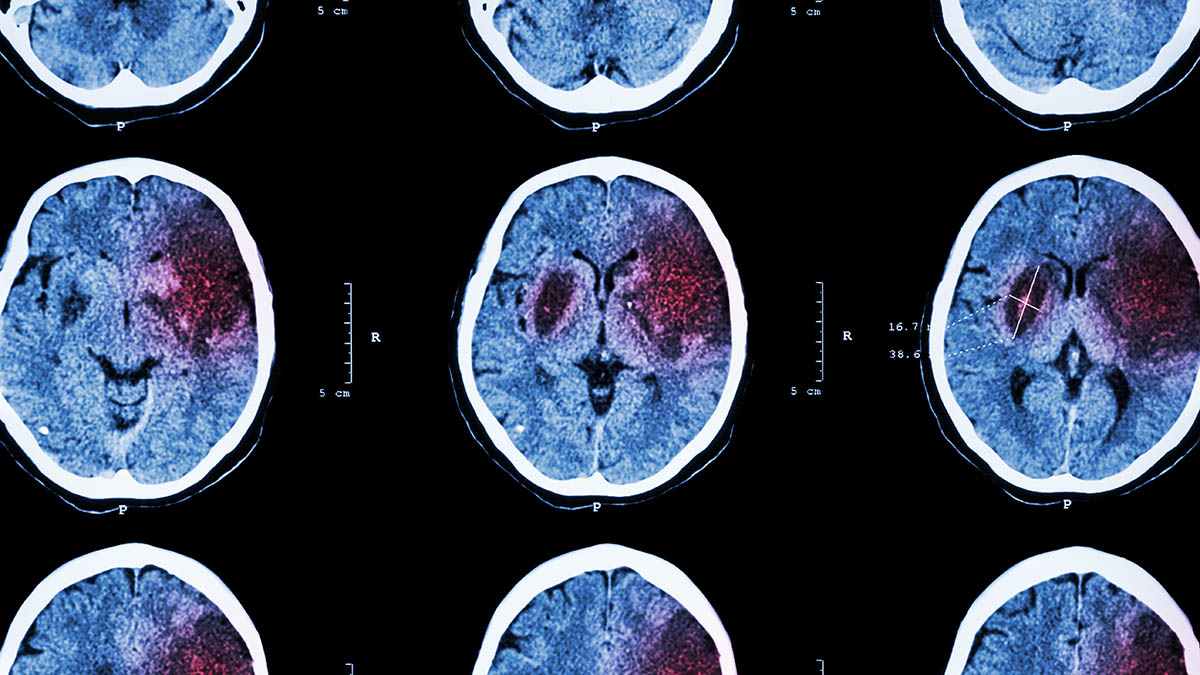

«Резкая вспышка»: врач перечислил симптомы, которые предупреждают о скором инсульте

Фото: Depositphotos

29 октября — день борьбы с инсультом. «Вечерняя Москва» узнала у кандидата медицинских наук Андрея Кондрахина, чем опасно это состояние, что ему может предшествовать и как можно профилактировать развитие инсульта.

Два вида

По словам эксперта, существует два вида инсульта.

• Первый вид — ишемический

— Ишемический инсульт в результате развития атеросклероза — это инфаркт мозга, нарушения связаны с атеросклеротической бляшкой или тромбом, который застрял в результате сужения сосуда. Факторов развития у этого много, но суть одна: ишемическая природа и нехватка крови приводят к уменьшению питания. При ишемическом инсульте выживаемость выше, — объяснил врач.

• Второй вид называется геморрагическим инсультом, или апоплексическим ударом.

— Этот вариант инсульта развивается очень быстро и обычно заканчивается смертью: происходит быстрый разрыв сосуда, начинается кровоизлияние в мозг, — предупредил Кондрахин.